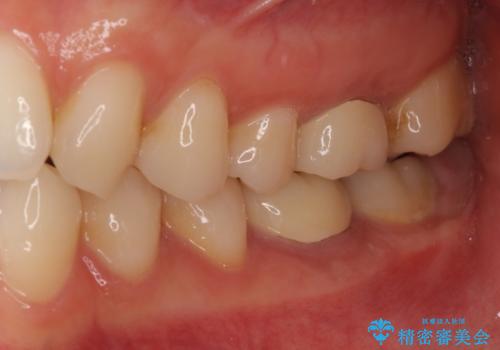

「違和感もなく、まるで自分の歯のようにしっかり咬めます!」と大変喜んで頂けました。

被せ物の種類:オールセラミッククラウン スタンダード